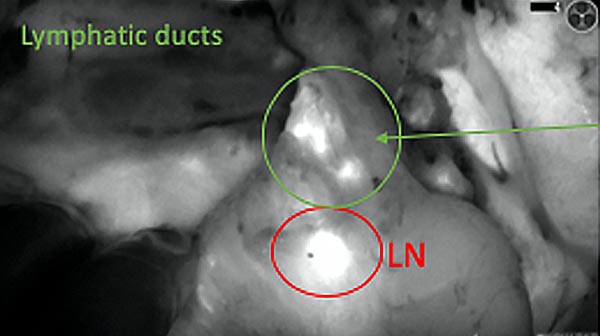

Intraoperative fluorescence imaging of the pancreas part that contains tumor

The tumor area light up fluorescently and so does a lymph node (LN; red circle) that is located on top of the tumor area. We can also see some lymphatic ducts (green circle).

After removal of the pancreas tumor fluorescence imaging was performed to check that there was no residual fluorescence left in the wound bed. A little bit of background fluorescence was found in the intestine.